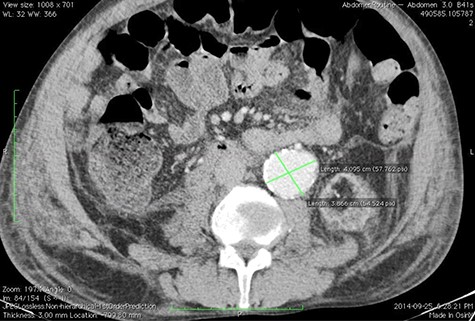

A 59-year-old male presented with end-stage liver disease secondary to hepatitis C and end-stage renal disease. On CT scan, an abdominal aortic aneurysm was incidentally found with a diameter of 4*3.8 cm (Fig. 1).